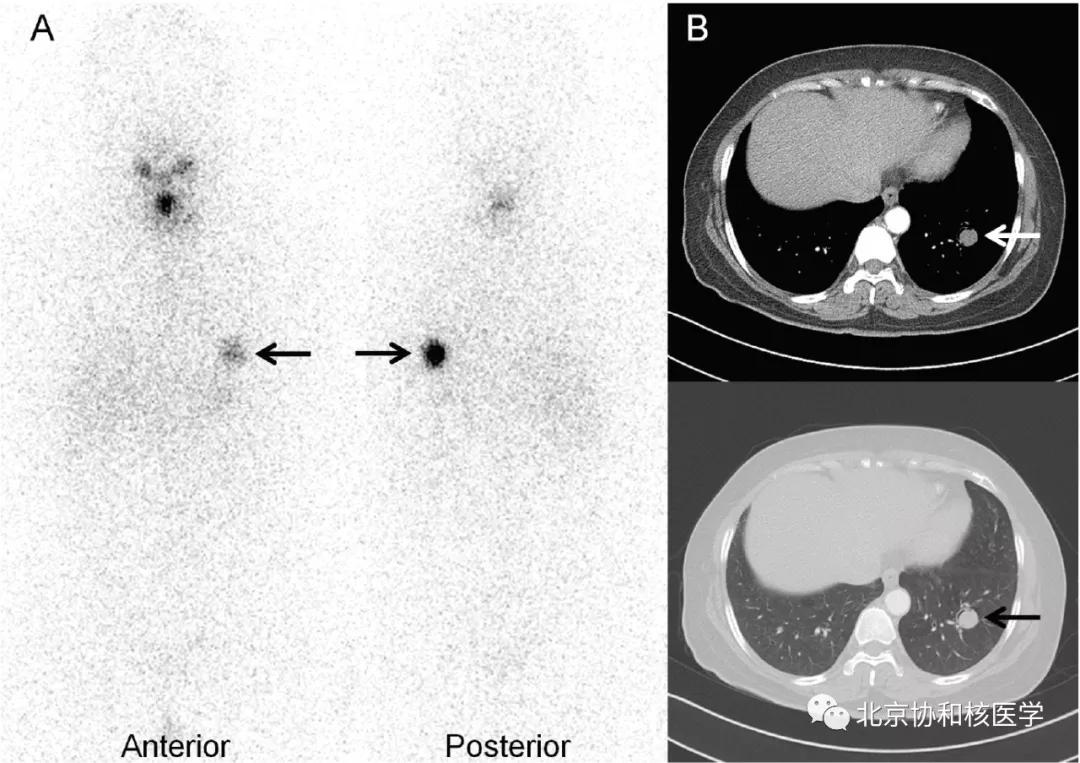

乳腺良性纤维瘤碘摄取:

肺鳞癌所致碘摄取(后位图像),同时可见颈部甲状腺残余病灶: